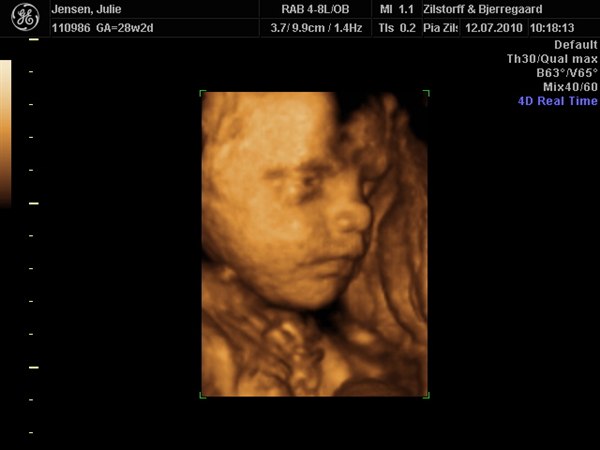

smilehuller og ligner helt sikkert Viktor

Kan slet ikke komme mig over hvor fantastisk det er at se det lille menneske inden i en

Vedhæftede fotos (klik for at se i fuld størrelse)